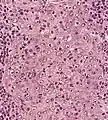

Undifferentiated nasopharyngeal carcinoma—low power Undifferentiated nasopharyngeal carcinoma—med. power

Undifferentiated nasopharyngeal carcinoma—med. power Undifferentiated nasopharyngeal carcinoma—high power

Undifferentiated nasopharyngeal carcinoma—high power Undifferentiated nasopharyngeal carcinoma—high power

Undifferentiated nasopharyngeal carcinoma—high power